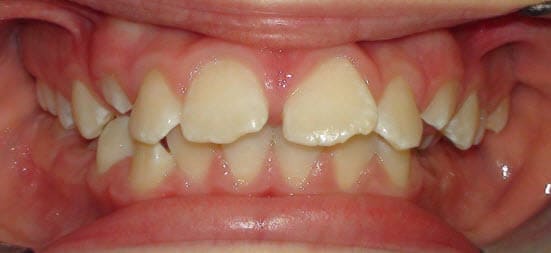

Petite patiente, 9 ans et demi.

j'avais essayé deux mois un bihélix mandibulaire il y a deux ans. Echec complet.

Je la revois aujourd'hui. Evidement, cela ne s'est pas arrangé.

J'avoue etre en panne d'option thérapeutique, a part la disjonction médiane au piezo. Des plaques à pistes ?

D'autres idées ? si chirurgie, vers quel age ?